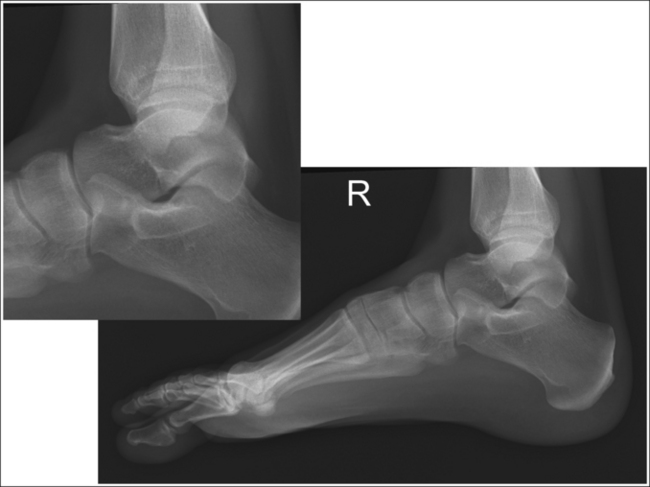

See Figure 6-39 and Box 6-9.

The calcaneus and distal tibia and fibula are in a lateral projection. The domes of the talus are superimposed, the tibiotalar joint space is open, and the distal fibula is superimposed by the posterior half of the distal tibia.

• To obtain a lateral calcaneal projection, begin with the patient in a supine position, with the leg extended (Figure 6-40) and the foot dorsiflexed until its long axis forms a 90-degree angle with the lower leg. Rotate the patient toward the affected leg until the lateral foot surface is against the IR; then, adjust the degree of rotation until the surface is aligned parallel with the IR (Figure 6-41). For most patients, this positioning places the lower leg parallel with the imaging table. If this is not the case, as with a patient with a large upper thigh, the foot and IR should be elevated to place the lower leg parallel with the imaging table.

• Talar domes: The domes of the talus are formed by the most medial and lateral aspects of the talar's trochlear surface. They are visible on a lateral calcaneal projection as domed structures that articulate with the tibia. When a lateral calcaneus projection has been obtained, the talar domes should be superimposed and appear as one, and the tibiotalar joint should be open. If the lateral calcaneus is mispositioned, the domes are individually demonstrated and obscure the tibiotalar joint. Misalignment of the domes will result from poor knee and foot positioning.

• Effect of lower leg positioning on talar dome superimposition. Often, if the knee is not fully extended (Figure 6-42) or if the distal tibia is not elevated to place the lower leg parallel with the IR (in a patient with a large upper thigh), the proximal tibia is positioned farther from the imaging table than the distal tibia. The resulting image demonstrates the lateral talar dome proximal to the medial talar dome, and the height of the longitudinal arch appears less than it actually is because the cuboid shifts anteriorly and the navicular bone moves posteriorly in this position; the talocalcaneal joint will be narrowed (see Image 27). If the distal tibia is positioned farther from the imaging table than the proximal tibia, the medial talar dome is demonstrated proximal to the lateral dome, and the height of the longitudinal arch appears higher than it actually is because the cuboid shifts posteriorly, the navicular bone moves anteriorly, and the talocalcaneal joint will be wider (see Image 28).

The midcalcaneus is at the center of the exposure field. The tibiotalar joint, talus, calcaneus, and calcaneus-articulating tarsal bones are included within the collimated field.

• Center a perpendicular central ray 1 inch (2.5 cm) distal to the medial malleolus to place the calcaneus in the center of the exposure field. Centering to the midcalcaneus better demonstrates the calcaneus and the surrounding calcaneotarsal and talocalcaneal articulations, allowing for accurate calcaneal inclination measurements and for visualization of calcaneal tuberosity displacement.